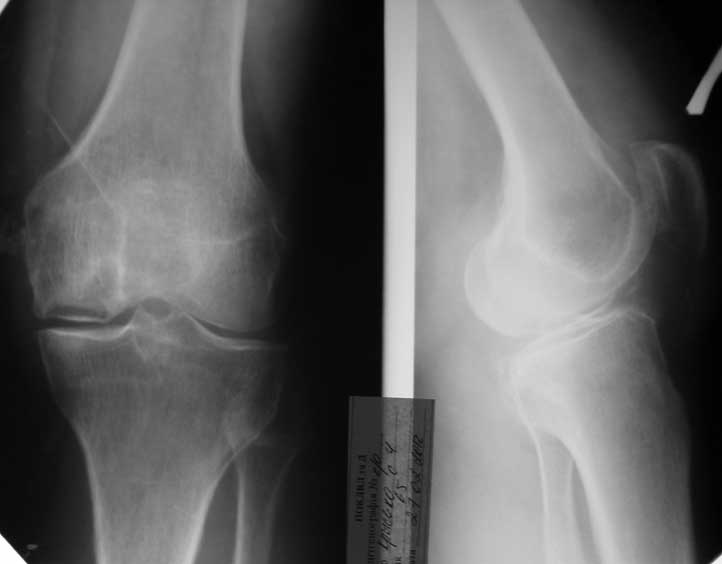

Пациэнтка 65 лет, жалобы на боли по вн. поверхности левого коленного сустава. Разгибани-згибание в полном обьеме. Из анамнеза: травма 6 мес. назад впала на коленный сустав. Не лечилась.

Узи: повреждения вн. мениска.

Планирую: 1- этап Артроскопию левого коленного сустава. 2- этап Уникондилярное ендопротезирование системой Oxford.